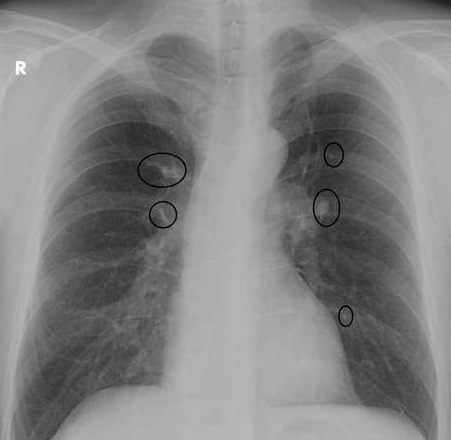

Симптомы и причины скопления воды в легких

Раздел: Ракурсы просвещения